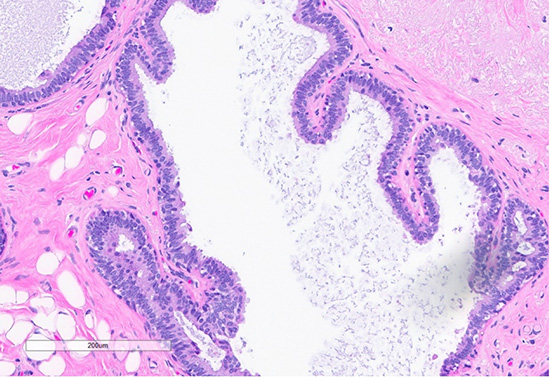

Figure 4: H&E section (top) shows a focus of usual ductal hyperplasia (UDH), characterized by expanded ducts filled with mildly polymorphous epithelial cells arranged in a haphazard pattern with irregular spaces. Scattered foci (bottom) exhibit features of columnar cell change, with the dilated ducts lined by columnar cells arranged perpendicularly to the basement membrane, with apical snouts.